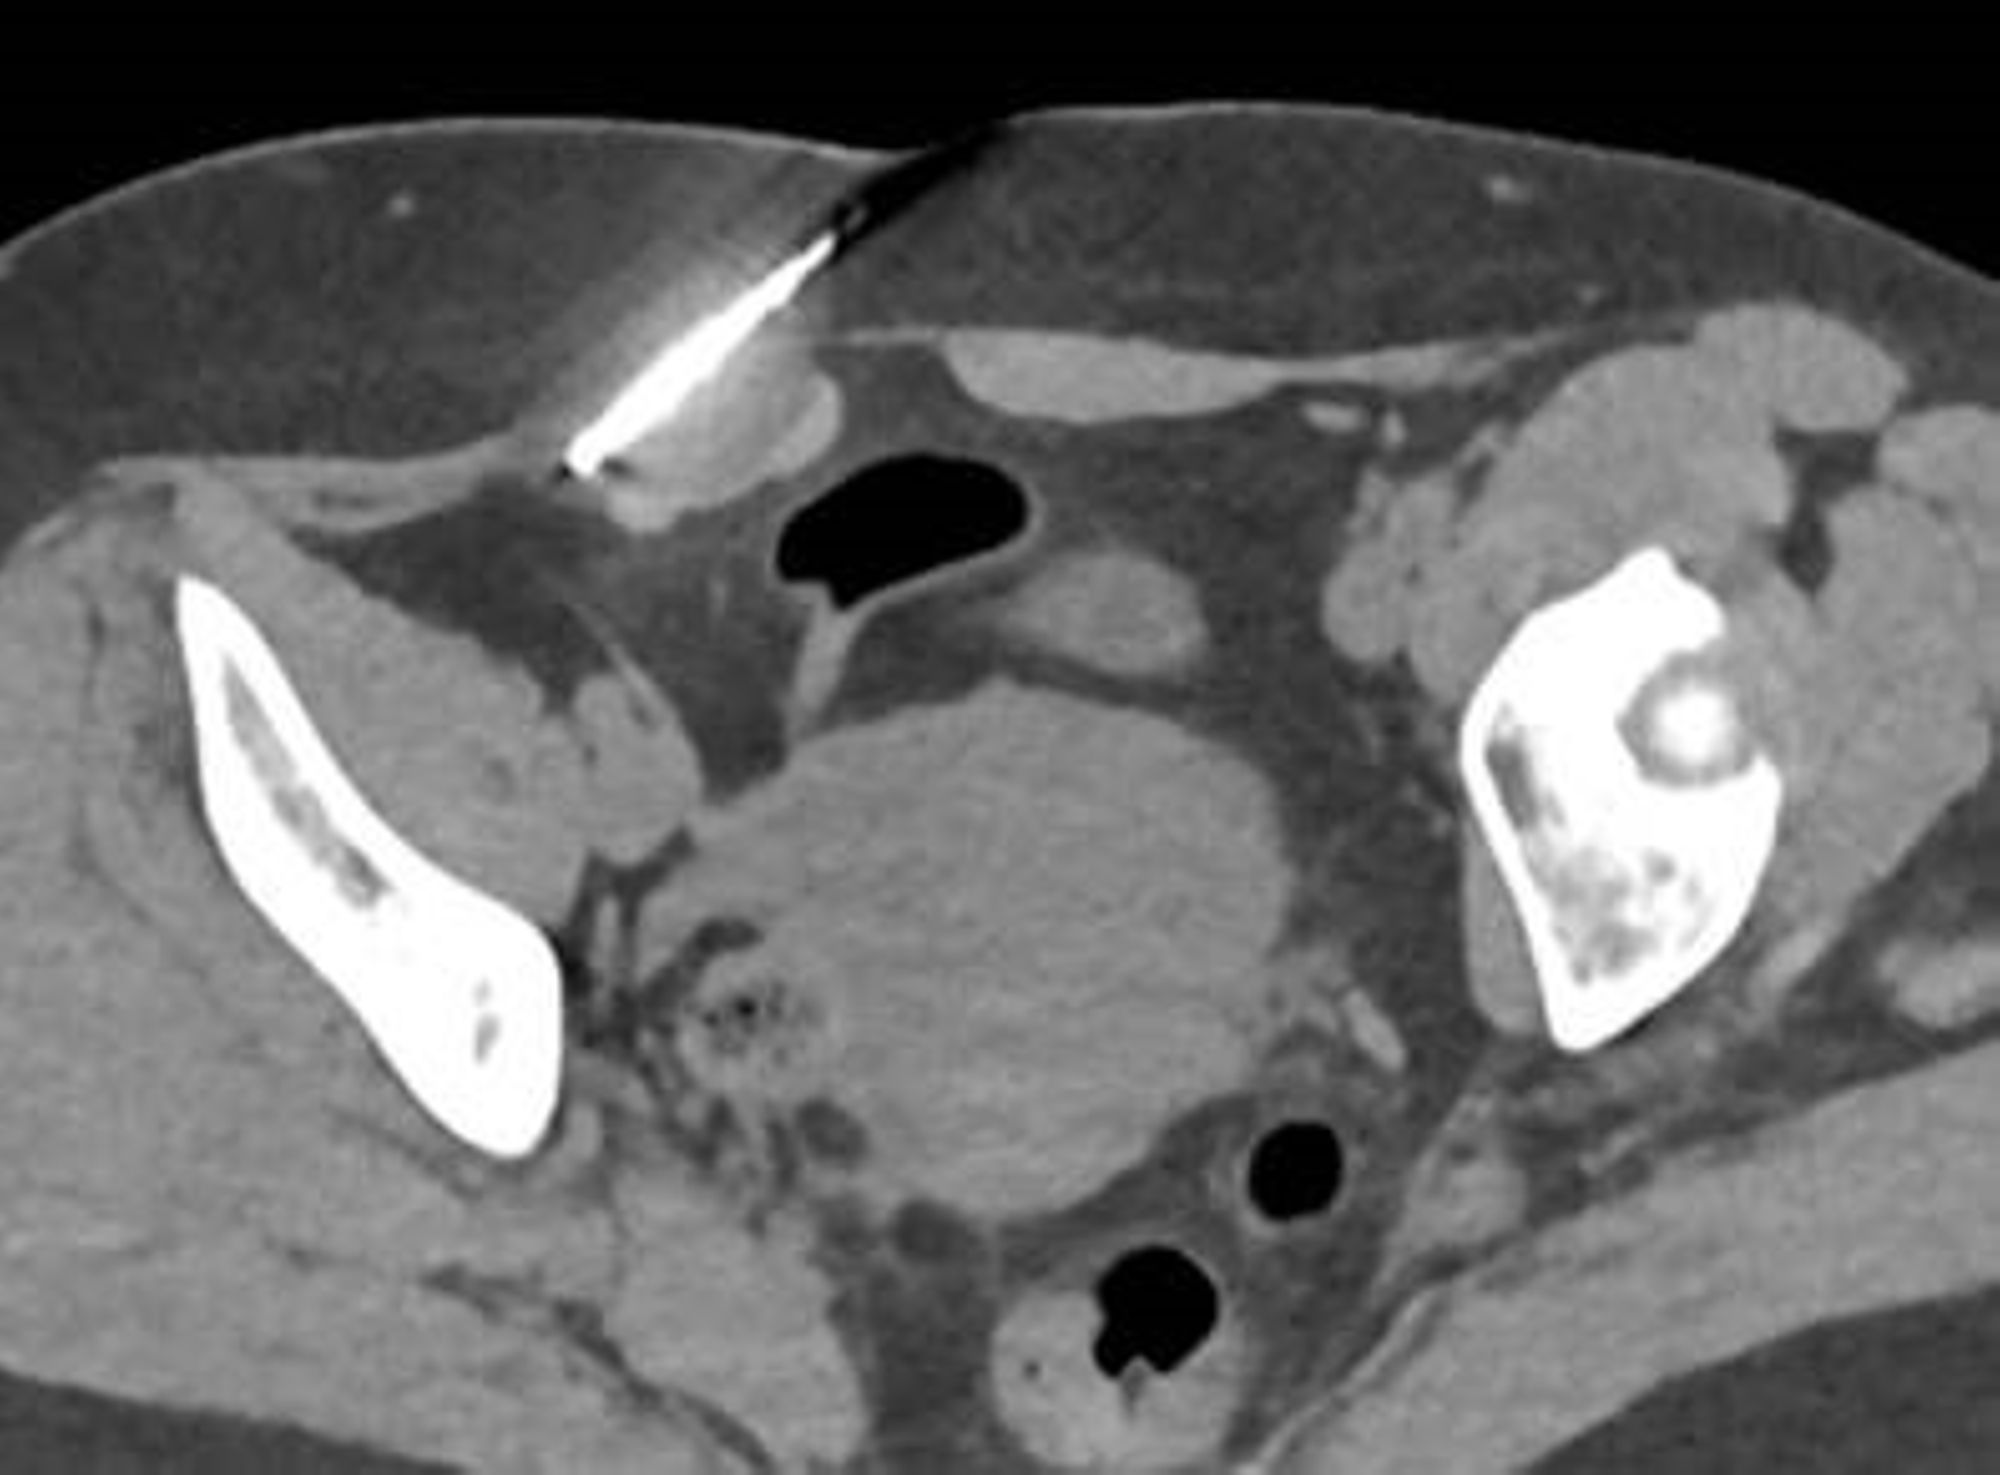

Les radiologues interventionnels de l'Hôpital peuvent désormais réaliser des cryothérapies de nodules d'endométriose pariétale en utilisant de manière mini-invasive le froid extrême (-40°C) pour leur traitement. Un glaçon va se former et faire ainsi nécroser la lésion et la dévasculariser. Le nodule va se résorber sous quelques semaines et ne plus réagir au cycle hormonal.

La cryothérapie permet leur traitement simple et rapide sans cicatrice, de manière mini invasive en alternative à la chirurgie, en préservant la paroi abdominale, le tout en ambulatoire.